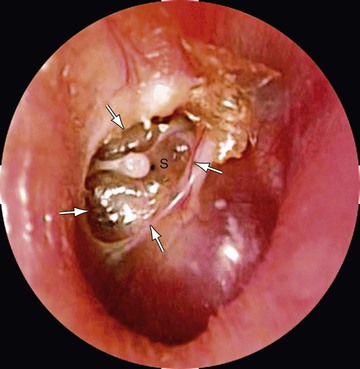

Cholesteatoma is a cyst-like growth originating in the middle ear, lined by keratinized, stratified squamous epithelium and containing desquamated epithelium and/or keratin (see Chapter 638; Fig. 640-8).

Acquired cholesteatoma develops most often as a complication of long-standing chronic OM. The condition also may develop from a deep retraction pocket of the TM or as a consequence of epithelial implantation in the middle-ear cavity from traumatic perforation of the TM or insertion of a tympanostomy tube. Cholesteatomas tend to expand progressively, causing bony resorption, often extend into the mastoid cavity, and may extend intracranially with potentially life-threatening consequences. Acquired cholesteatoma commonly presents as a chronically draining ear in a patient with a history of previous ear disease. Cholesteatoma should be suspected if otoscopy demonstrates an area of TM retraction or perforation with white, caseous debris persistently overlying this area. Along with otorrhea from this area, granulation tissue or polyp formation identified in conjunction with this history and presentation should prompt suspicion of cholesteatoma. The most common location for cholesteatoma development is in the superior portion of the TM (pars flaccida). Most patients also present with conductive hearing loss on audiologic evaluation. When cholesteatoma is suspected, otolaryngology consultation should be sought immediately. Delay in recognition and treatment can have significant long-term consequences, including the need for more extensive surgical treatment, permanent hearing loss, facial nerve injury, labyrinthine damage with loss of balance function, and intracranial extension. The required treatment for cholesteatoma is tympanomastoid surgery.

Congenital cholesteatoma is an uncommon condition generally identified in younger patients (Fig. 640-9). The etiology of congenital cholesteatoma is thought to be a result of epithelial implantation in the middle-ear space during otologic development in utero. Congenital cholesteatoma most commonly presents in the anterior-superior quadrant of the TM but can be found elsewhere. Congenital cholesteatoma appears as a discrete, white opacity in the middle-ear space on otoscopy. Unlike patients with acquired cholesteatoma, there is generally not a strong history of OM or chronic ear disease, history of otorrhea, or changes in the TM anatomy such as perforation or retraction. Similar to acquired cholesteatoma many patients do have some degree of abnormal findings on audiologic evaluation, unless identified very early. Congenital cholesteatoma also requires surgical resection.